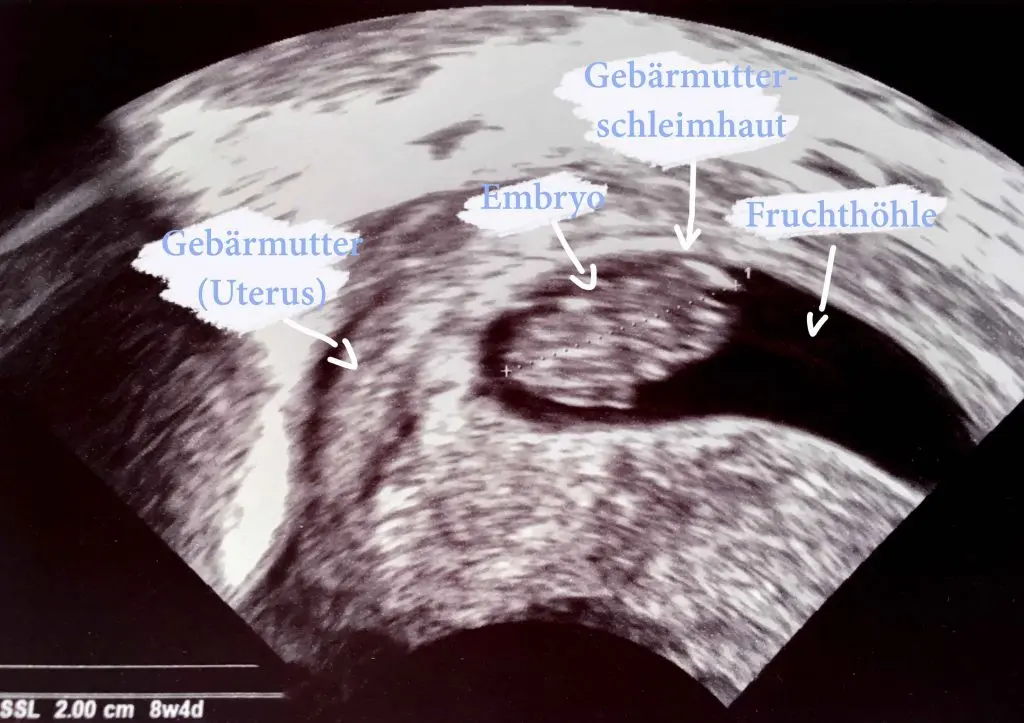

Was kann man im Ultraschall der Gebärmutterschleimhaut sehen?

Im Ultraschall der Gebärmutterschleimhaut kann der Arzt Folgendes beobachten:

- Dicke der Gebärmutterschleimhaut: Die Dicke der Schleimhaut ist ein wichtiger Indikator für die Einnistung der Eizelle. Eine Dicke von 7 bis 8 mm gilt als optimal.

- Struktur der Gebärmutterschleimhaut: Die Schleimhaut sollte eine gleichmäßige Struktur aufweisen. Anomalien wie Polypen oder Myome können die Einnistung der Eizelle beeinträchtigen.

- Einnistung der Eizelle: Der Ultraschall kann die Einnistung der Eizelle in der Gebärmutterschleimhaut sichtbar machen.

- Fruchthöhle: Ab der Schwangerschaftswoche ist die Fruchthöhle im Ultraschall sichtbar.

- Embryo: Ab der Schwangerschaftswoche ist der Embryo im Ultraschall sichtbar.